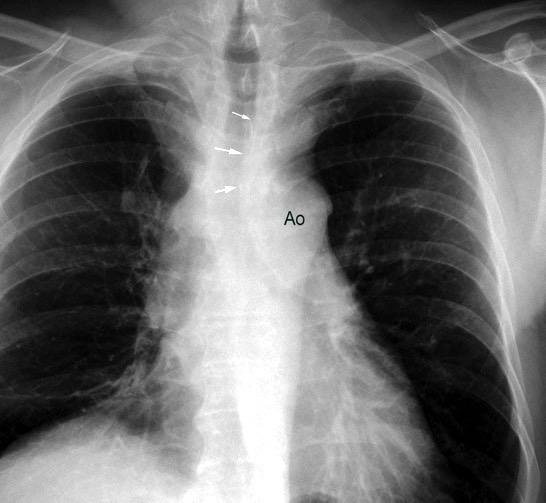

85. ENSANCHAMIENTO MEDIASTÍNICO AGUDO

117. MASA MEDIASTÍNICA DE DENSIDAD AGUA

Hematoma intramural

Disección aórtica

Rotura de aneurisma aórtico

Mediastinitis aguda

TRAUMA

Rotura esternal

Hematoma mediastínico

Rotura aórtica

Fractura vertebral

Rotura esofágica Perforación esofágica